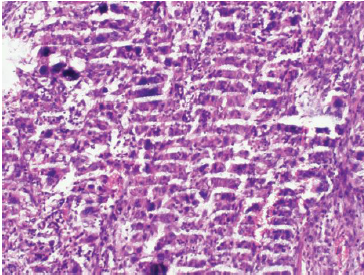

七、切片染色效果不佳

切片染色效果不佳可能是由于染色時間過長或過短、染色液濃度不合適等原因造成的。

為了改善染色效果,我們可以按照以下步驟進行調整:

①根據實驗需要,選擇合適的染色液種類和濃度。

②控制染色時間,確保染色充分且不過度。